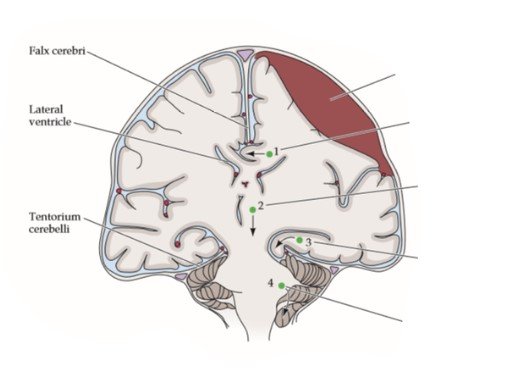

Analisem a imagem abaixo e associam os números com o tipo respectivo de herniação cerebral encontrada na descompensação da hipertensão intracraniana:

( ) Hérnia Tonsilar

( ) Hérnia do Cíngulo ou Subfalcina

( ) Hérnia Central

( ) Hérnia de Uncus

D. 4 - 1 - 2 - 3

CORRETO :

Gabarito: D